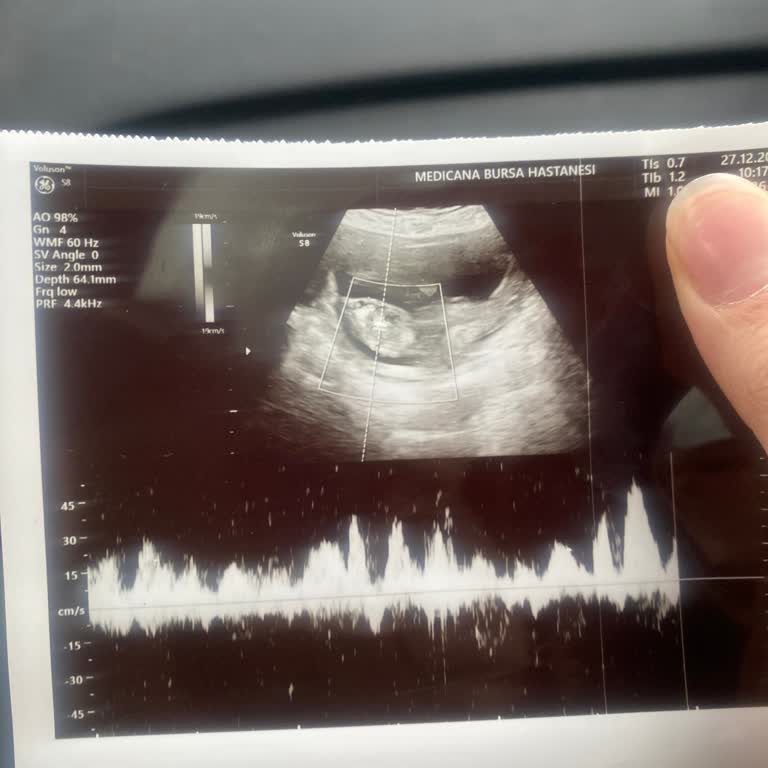

29.10.2025 tarihinde kızım Bursa Medicana Hastanesi’nde dünyaya geldi. A‑B‑0 kan uyumsuzluğu sebebiyle sarılık değeri üst sınıra yakın olmasına rağmen bizi taburcu ettiler. Doğumdan sonraki ilk çocuk doktoru randevusunda, N**** K*** Ö***’ın kontrolünde, üst sınır 16 iken bebeğimin değeri 16,6 çıkınc...